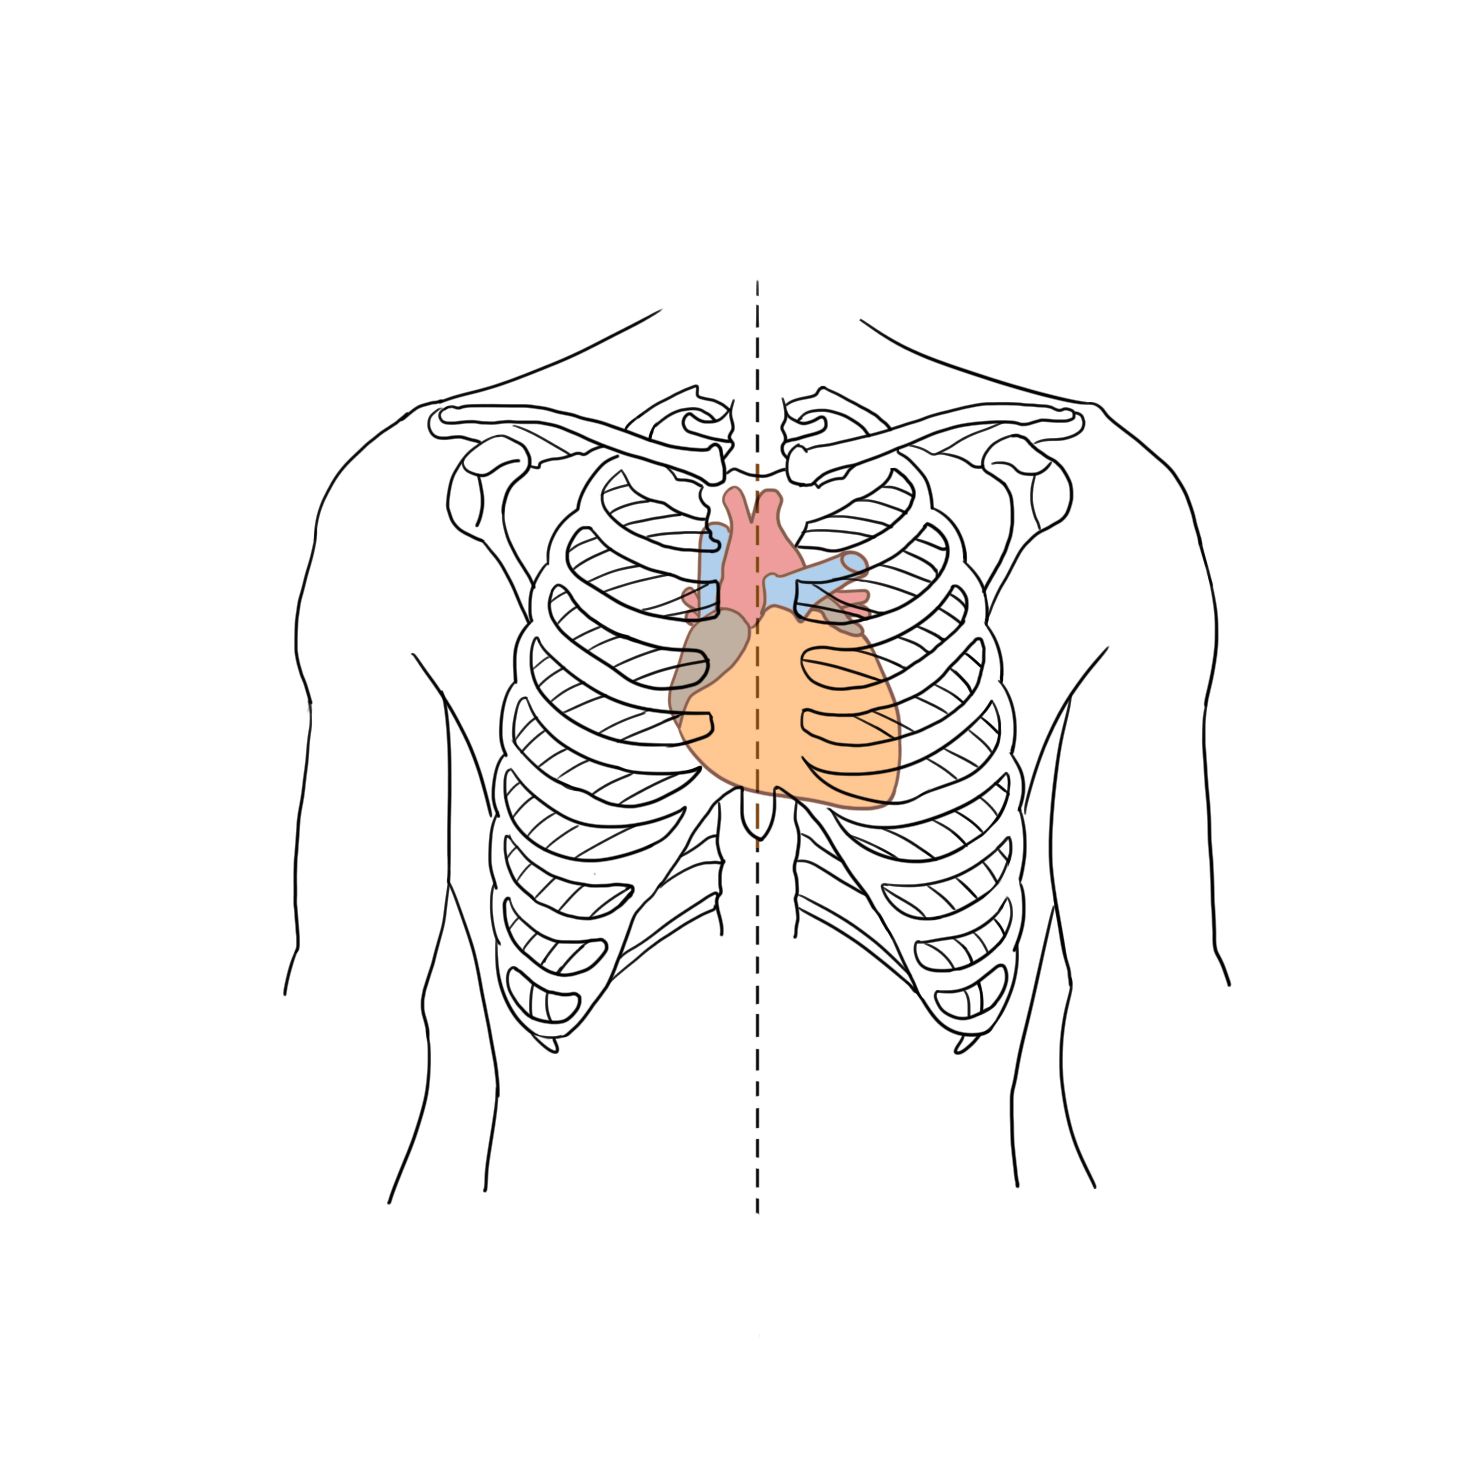

위치가슴의 왼쪽에 위치하며 흉골을 기준으로 왼쪽으로 2/3, 오른쪽으로 1/3이 위치하게 됩니다.